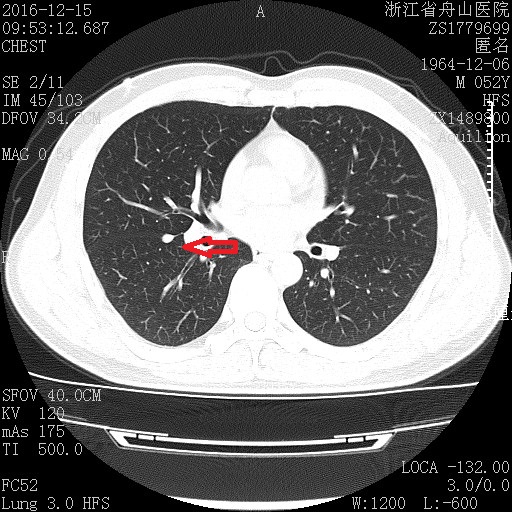

男性患者,52岁,体检发现右肺结节一个月(图1),要求进一步检查来院就诊。

图1

令人欣喜的是经过三维重建,发现右肺结节是叶间胸膜肥厚(图2)。

图2